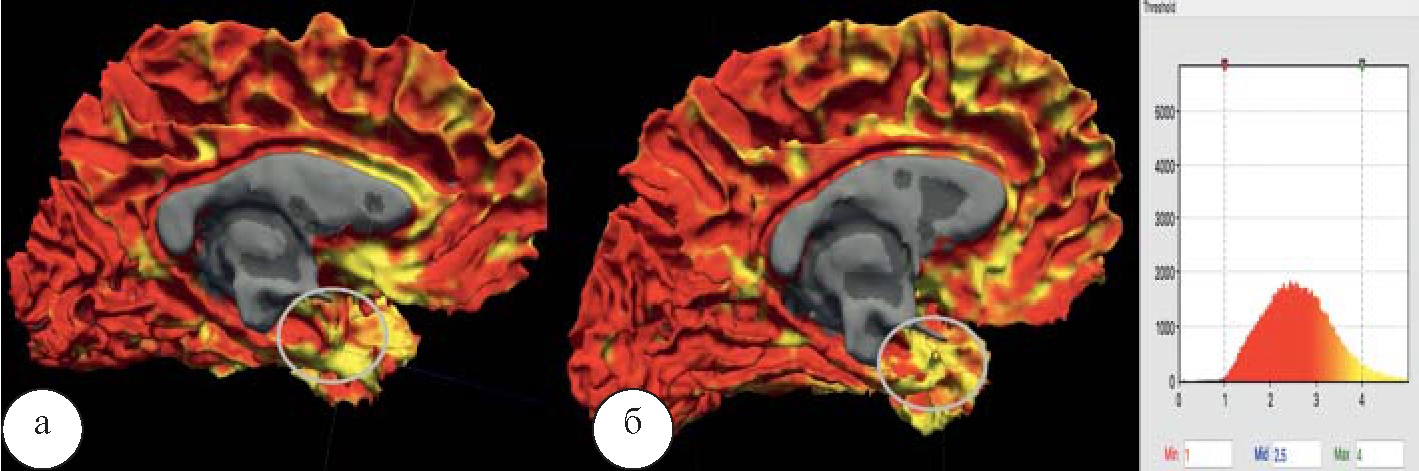

При моделировании объемного коннектометрического изображения отчетливо визуализируется обеднение функциональных связей СПРР по сравнению с нормой (рис. 1).

Рис. 1. Функциональные связи СПРР: а – в группе пациентов, находящихся в состоянии короткой ремиссии; б – картина нормальной коннективности, p<0,05

С целью формирования объективных диагностических критериев для снятия диагноза наркомании в экспертной работе, в дальнейших наших исследованиях представится возможным подтвердить восстановление нормального функционального коннектома при более длительных сроках ремиссии у наркозависимых.